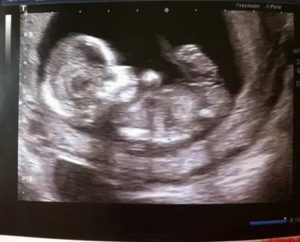

Чтобы определить пол ребенка с помощью УЗИ, 12 неделя беременности — оптимальный срок. К этому времени с высокой точностью можно узнать, сын или дочка пополнит семью. Сейчас мама может увидеть своего малыша. Поскольку плод еще мал, без помощи врача женщина на УЗИ не сможет рассмотреть детали.

Специалист объяснит, как чувствует себя малыш, и поможет рассмотреть фото, где удастся разглядеть голову и тельце ребенка, крохотное личико с глазками. Эмбрион еще малоподвижен, что иногда затрудняет диагностику пола ребенка. При неудачном расположении плода определение половой принадлежности проведут в ходе второго скрининга.

При проведении УЗИ будущие родители могут увидеть свою крошку, плод на 12 неделе беременности уже выглядит так, что даже не специалист разберется, где у него голова, а где конечности.

А вот пол ребенка на этом исследовании определить удается далеко не всегда, поскольку плод еще слишком маленький.

На снимке можно увидеть отдельные части тела плода — голову, конечности, туловище. Прослеживаются формирующиеся черты лица. Длина костей носа — важный показатель определения генетических аномалий.

Хорошо заметны печень, почки, сердце, позвоночник. Перепонки между пальцами исчезают. Заканчивается формирование половых органов. Если ребенок лежит, не закрывая ручками область промежности, врач может определить, мальчик это или девочка.

На этом сроке впервые можно увидеть ребенка целиком, оценить анатомическое строение плода, выявить наличие/отсутствие серьезных пороков развития.